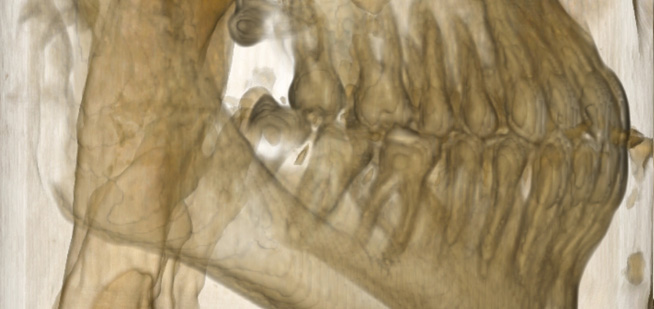

Endo-Perio

Der Facharzt für Endodontie und Periodontologie benötigt Bilder von absoluter Spitzenqualität und Detailschärfe, um Verfahren wie die Behandlung von Zahnbrüchen, die Heilung von Zahngewebe und die Therapie des Kieferkanals vorzunehmen, da er über genaue Details der behandelten Zone und des Krankheitsbilds verfügen muss, um eine wirkungsvolle Behandlung planen zu können. Nur eine eingehende Untersuchung der betroffenen Areale kann Aufschluss über einen mehr oder weniger invasiven Eingriff geben.